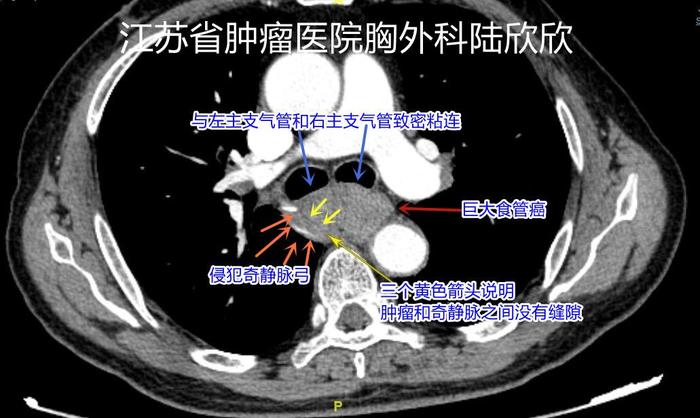

下面是患者的术前CT,我结合术中所见解说如下:

上图,棕红色箭头指示的是巨大食管癌。四个橙色箭头和3个黄色箭头之间指示的是奇静脉弓,与肿瘤之间似乎有一道细细的缝隙。实际,手术中看,肿瘤侵犯奇静脉弓。手术中切除了奇静脉弓。两个蓝色箭头指示的是肿瘤与左主支气管和右主支气管关系很密切。手术中,肿瘤没有侵犯左主支气管和右主支气管,只是靠的非常近。

上图,右下角的两个黄色箭头指示的白色圆圈是降主动脉,是人体最粗的大动脉。右边的两个橙色箭头指示的是肿瘤侵犯降主动脉外膜,手术中小心翼翼将肿瘤和淋巴结和降主动脉放开,局部降主动脉外膜被切除。下方的黄色箭头指示的是降主动脉和脊柱夹角中叶有肿瘤组织,导致胸导管被侵犯,术中切除4-5厘米长的胸导管。左下角的蓝色箭头指示的是肿瘤侵犯右肺,手术中切除了局部右肺。上面的4个棕红色箭头指示的是巨大食管癌与左主支气管和右主支气管关系很密切。手术中,肿瘤没有侵犯左主支气管和右主支气管。